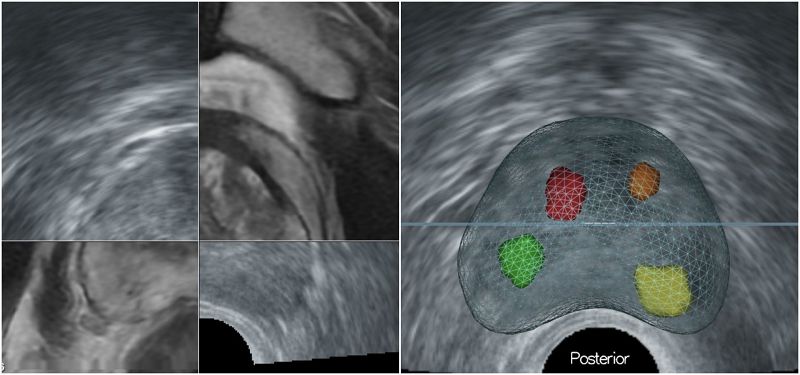

傳統經直腸隨機切片方式猶如「盲抽」,可能誤判為良性或需重複切片。MRI雖能判讀可疑病灶,卻難以即時定位;超音波則無法準確辨認病灶,因此最適切的診斷方式是將兩種影像融合後,進行導引切片。台北慈濟醫院泌尿科團隊導入軟體輔助影像融合切片技術,先由MRI標記病灶,再於即時超音波中進行影像疊合與校準,鎖定病灶進行經會陰切片,大幅提升精準度,並因避開直腸入針,大幅降低感染與敗血症風險,惟檢查時需全身麻醉。鐘伯恩醫師與台北慈濟醫院泌尿科團隊將此種檢查方式的臨床研究成果發表於國際泌尿科醫學期刊《The Journal of Urology》與《Urological Science》,研究顯示,影像融合誤差超過5%時,容易導致低估病灶分期,而使用「軟體輔助」影像融合攝護腺切片,可於目標區域增加約20%的癌症診斷率。與傳統經直腸切片的技術相比,能有效提高切片精準度。